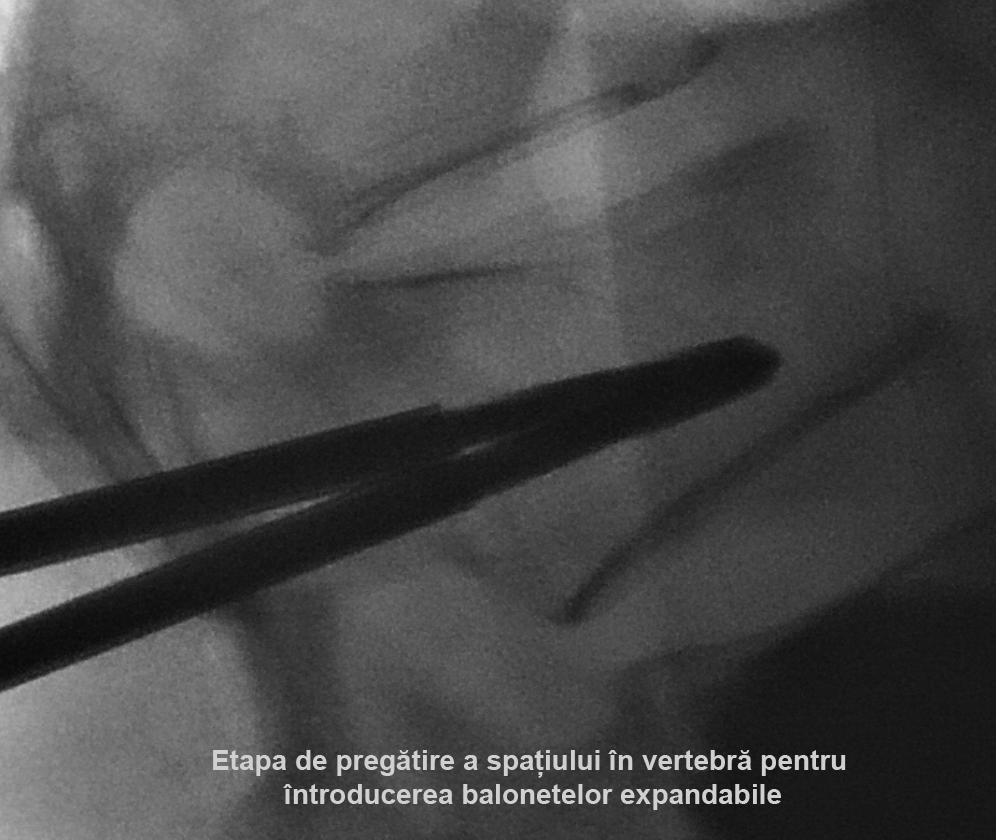

Kyfoplastia reprezintă o procedură minim invazivă în timpul căreia chirurgul introduce în corpul vertebral un tub cu un balon expandabil. Sub control fluoroscopic are loc expansionarea balonului în corpul vertebral, cu restabilirea înălţimii corpului vertebral şi corijarea diformităţii kifotice. Ulterior, în cavitatea formată de balon, se introduce cimentul acrilic, ceea ce contribuie la consolidarea vertebrei.

Realizarea intervenţiilor percutanate de acest tip presupune utilizarea unui fluoroscop intraoperatoriu, cu scopul de a reduce la minim complicaţiile (cum ar fi, leziuni ale structurilor nervoase, scurgerea cimentului extracorporeal, embolii venoase, etc.). În cazul pacientei noastre, a fost utilizată instalaţia de Angiografie tridimensională (3D) Siemens ”Artis Zee”, disponibil în sala de operaţii Hybrid a Spitalului Clinic Republican, care asigură o calitate excepţională a imaginilor intraoperatorii.